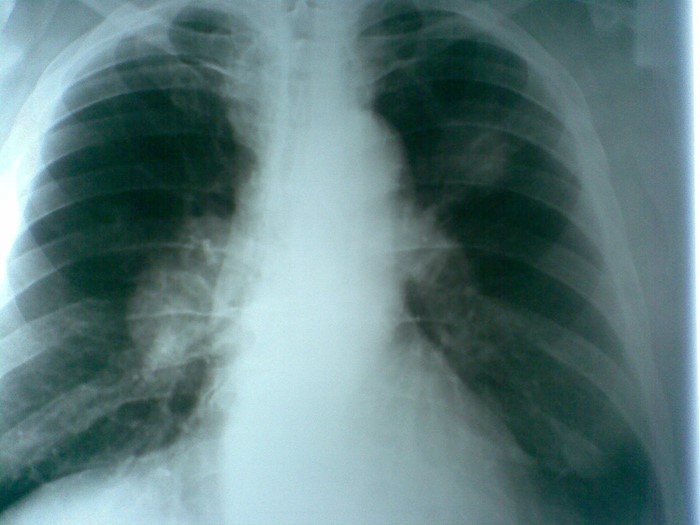

Поздно диагностированные случаи: 3, 4 стадии

Для рака лёгких поздно диагностированными считаются случаи выявления заболевания на 3 и 4 стадиях. Согласно классификации TNM четвёртая стадия ставится в случае появления отдаленных метастазов (М). При этом может быть любая Т и N.

Если первые две стадии имеют более благоприятный прогноз, то в случае с запущенными вариантами по статистике выживают в течение пяти лет только 30 и 15% (соответственно 3 и 4 стадиям) заболевших.

Что пишут в КТ при раке легких?

На снимках КТ можно обнаружить опухоль, скопление жидкости или увеличенные лимфатические узлы еще до появления симптомов. Рентген грудной клетки и цитологическое исследование мокроты не считаются методами скрининга диагностики рака лёгких. Важно знать, что скрининг нужен не всем.